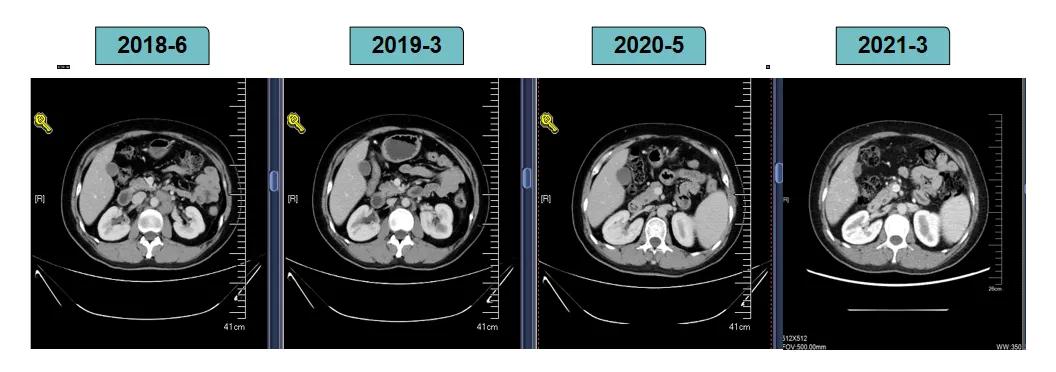

影像学评估-腹膜后淋巴结: